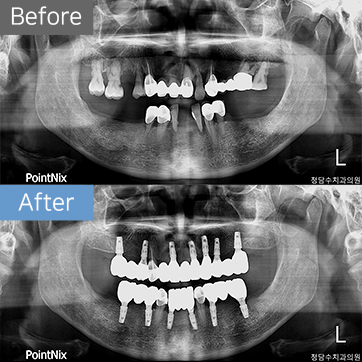

50대여 임플란트